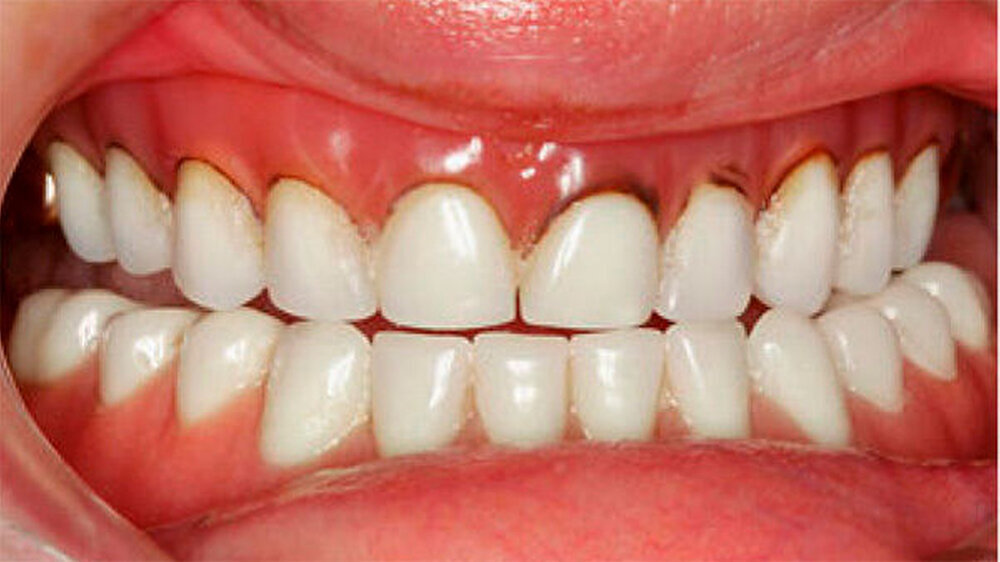

Die Patientin war mit einer knapp neunjährigen Teilprothese im Ober- und einer zweijährigen Totalprothese im Unterkiefer versorgt. Beim Lachen wurden die nicht mehr altersentsprechenden Prothesenzähne mit den deutlichen Randverfärbungen ersichtlich (Abb. 19). Das sagittale Wachstum des zahnlosen Unterkiefers führte in den letzten zwei Jahren aufgrund der verstärkten Kontakte im Frontzahnbereich zu einer beidseitigen Nonokklusion im Seitenzahnbereich (Abb. 20). Eine rasche Verbesserung der Ästhetik als auch der Funktion war unbedingt angezeigt, um das Selbstbewusstsein dieses puberalen Mädchens zu stärken.